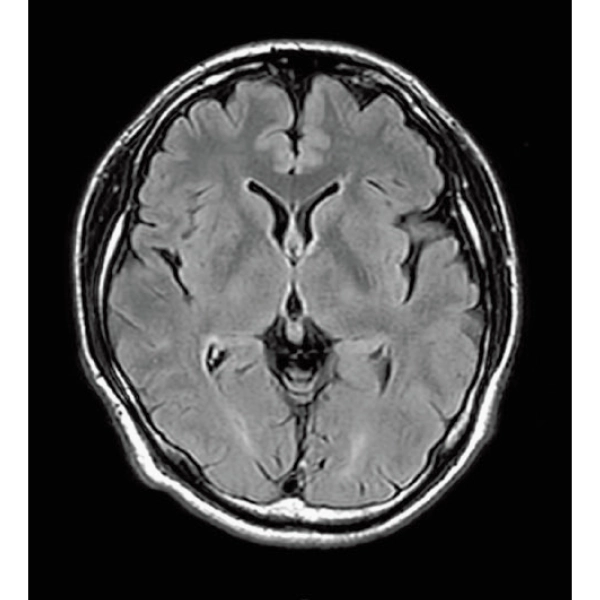

ShortScan

FLAIR, 1:14

StillShot:The camera detects motion and suppresses the effects of body movement

FLAIR

RADAR:Body movement suppression technology for those who cannot hold still

T2*WI RADAR, 2:34